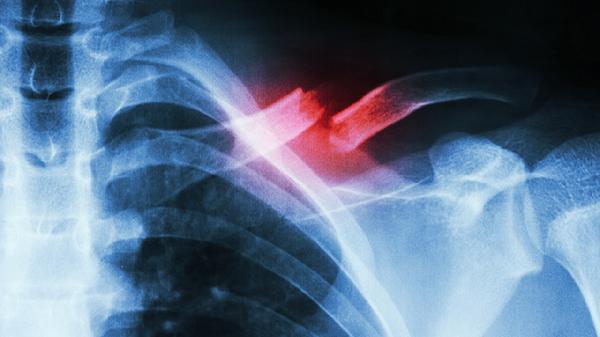

胸口左边疼痛可通过调整姿势、热敷缓解、药物干预、检查心脏问题、心理疏导等方式改善。胸口左边疼痛通常由肌肉拉伤、胃食管反流、心绞痛、肋软骨炎、焦虑等因素引起。

突发性压榨样疼痛伴冷汗需警惕心绞痛或心肌梗死,可能与冠状动脉狭窄有关。典型表现为运动后胸骨后疼痛向左肩放射,可通过心电图、冠脉CTA等检查确诊。高危人群应随身携带硝酸甘油片。